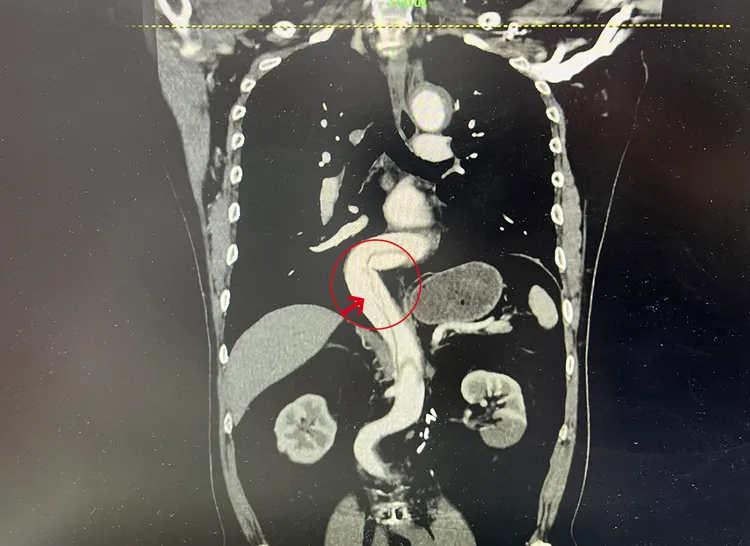

箭頭指出的長黑影,為腹部動脈破裂情形。院方提供

狀況稍穩定後,立即做主動脈血管斷層攝影,顯示患者從胸大動脈、腹部動脈、左側腎動脈,到左下肢髂動脈,一路破裂至少40公分長,血液撐裂血管內層,導致血管外層鼓漲成假腔,假腔內已積血約100西西,隨時有破裂的可能,一旦大破裂,死亡率高達90%。